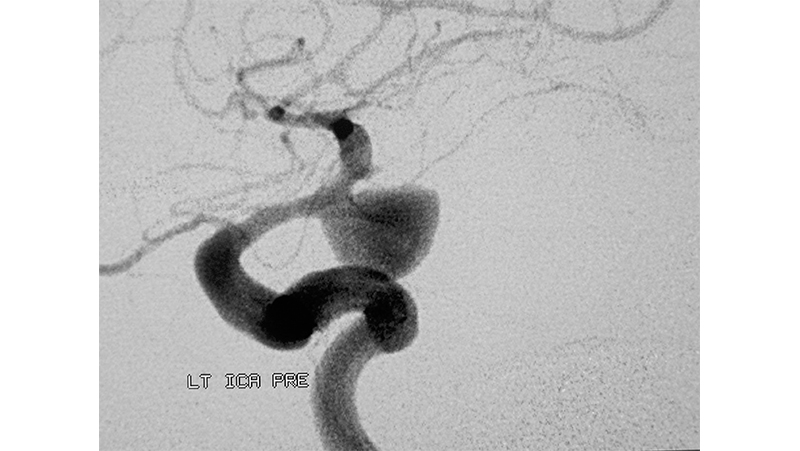

Εικόνα 1: Ραγέν ανεύρυσμα αριστερής οπισθίας αναστομωτικής αρτηρίας. Φαίνεται ήδη εγκατεστημένος έντονος αγγειόσπασμος στην υπερκλινοειδή έσω καρωτίδα, στο Α1 και Μ1 τμήμα της προσθίας και μέσης εγκεφαλικής αρτηρίας και σε περιφερικότερους κλάδους, με ελάττωση της διαμέτρου των αγγείων.